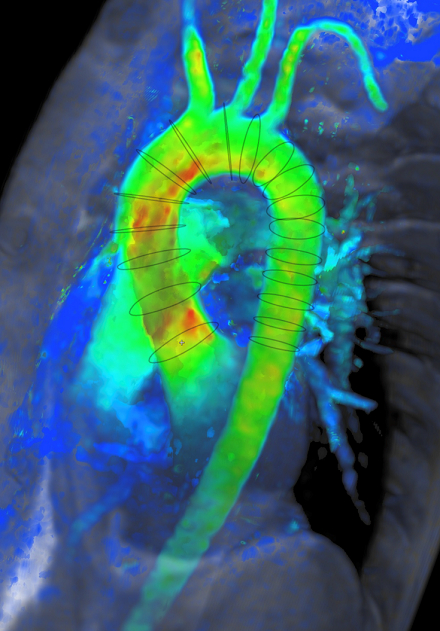

Methods We acquired both 4D flow brain MRI and 4D flow cardiac MRI in a single session using a Siemens 3T Magnetom Vida scanner in 5 volunteers (4 male, 1 female) 31.2 ± 10.4 years old. Using a compressed sensing protocol (R=7.7) each 4D flow scan was acquired in under 15 minutes. Brain and cardiac MRI respectively used a 1.4 mm3 and 2.1 mm3 voxel size; velocity was encoded in 3D at 120 cm/s and 200 cm/s, with 15-25 cardiac phases. 4D flow brain coverage included the ICA, BA, MCA, ACA, and PCA (Fig 1). 4D flow cardiac coverage included the ascending and descending thoracic aorta (Fig 2). 4D flow data were reconstructed using Tempus Pixel (Tempus, IL) and regions of interest were defined to measure volumetric flow rate (Q). Blood flow pulsatility over the cardiac cycle was quantified using pulsatility index (PI). Pearson’s correlation coefficient (r) was calculated for statistical analysis.